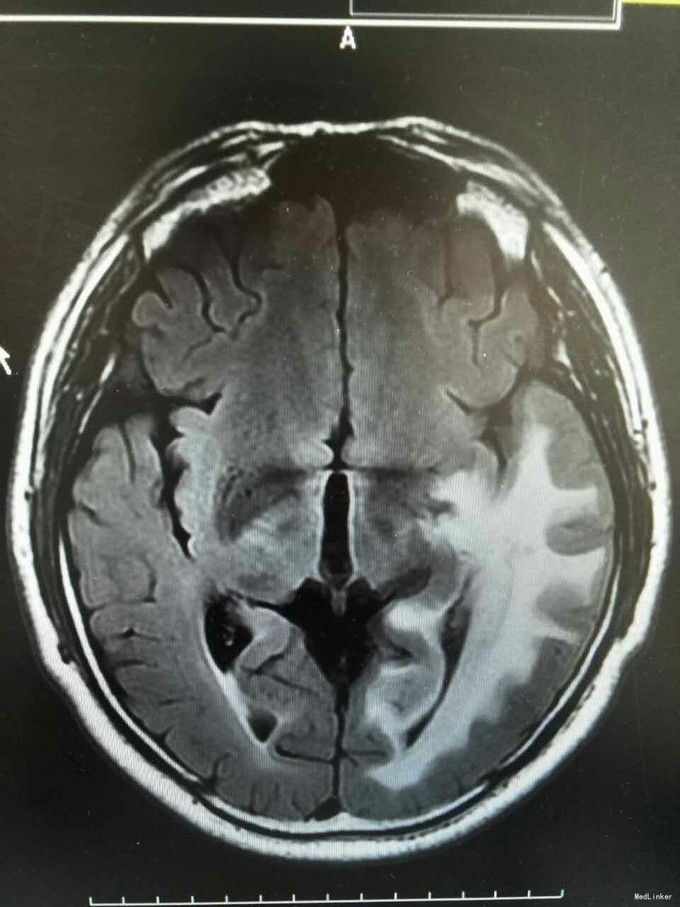

患者姜磊,男,49岁,主因"发作性视野缺损、失认8年余"于2015-11-20再次入我院,患者缘于8年前无诱因出现发作性视野缺损,伴阅读能力、理解力、认知能力下降,每次发作症状持续约3-5分钟左右,可自行缓解,无意识丧失、视物旋转、言语不利,无肢体活动障碍、大小便失禁。入院复查头颅MRI平扫+增强示:原左侧小脑幕、颞叶炎症治疗后,与2014-09-10日片比,病灶较前增多、增大。8年来间断在我院以:颅内非特异性炎症、症状性癫痫、高血压病 住院治疗,患者症状时轻时重,病灶反反复复,激素治疗有效。 病史汇报: 于2007年12月12日因"发作性视野缺损、失认1月"入我院,查头颅MRI示:左侧幕上颞底片状异常信号,并局部强化,考虑:炎症可能,肿瘤不排除;行腰穿检查,颅压120mmH2O ,外观清亮,脑脊液常规、生化均正常。脑电图轻度异常。给予复方磺胺甲恶唑片、青霉素、阿昔洛韦、激素(醋酸泼尼松片)等治疗。 2008年1月8日复查头颅MRI示:原左侧幕上颞底炎性病变范围缩小,综合考虑原颅内病变为炎性病变。于2008年1月19日出院,共住院37天。出院后仍间断出现发作性视野缺损症状。于2008-5-6复查头颅MRI示原左颞叶病变范围有缩小,支持局灶性脑炎的诊断。于2008.5.22~6.12予青霉素480万单位2/日巩固治疗30天。鉴于反复出现发作性视野缺损症状,于2008.6.5诊断性服用卡马西平片后上述症状未再发作,于是坚持服用卡马西平片(0.1g3/日)1年,服药期间未再出现发作性视野缺损症状。 于2012-05-29再次因"发作性双眼右侧视野缺失、闪烁感6天"入院,查头颅MRI示:原左侧幕上颞叶病变治疗后改变,考虑为炎性病变,结核可能。行腰穿示压力125mmH2O,脑脊液常规:颜色:无色,透明度:水样透明,潘氏试验:阴性,红细胞计数:80×106/L,白细胞计数:0x106/L,单个核细胞75%,多核细胞20%,脑脊液生化:蛋白508mg/L,葡萄糖3.3mmol/L,氯化物115.4mmol/L。脑电图印象:基本节律为低-中幅的α波, 频率调幅调节欠佳,分布可,左侧枕区波幅可见较右侧枕区减低。头前区可见少量低幅θ波及β波。深呼吸中见4-5hz慢波增多,有时呈短至中程节律,头前区为著,左侧偏胜。深呼吸后恢复好。睁闭眼试验:半抑制。闪光刺激:未见异常。脑电地形图:以α功率为主,可见θ功率。结论:轻度弥慢性异常脑电图及地形图;给予改善循环、营养神经、活血化瘀、脱水、激素等对症治疗。住院期间未再出现上述发作。 于2013-1-5再次因"发作性双眼右侧视野缺失、闪烁感1周。"入院,行头颅MRI示:左侧颞叶病变治疗后改变,与2012-07-24日片比,左侧小脑幕病变较前增大,左侧颞叶出现新病灶。给予改善循环、营养神经、活血化瘀、抗癫痫、抗感染(青霉素)、激素冲击(甲强龙)治疗后病情好转,于2013-4-15复查头颅MRI病灶再次缩小。患者出院后上述症状仍偶有发作。 于2014-5-12、2014-9-10复查头颅MRI病灶有增大趋势,再次给予抗炎(激素)等对症治疗后,于2014-11-24再次复查头颅MRI示:原左侧小脑幕、颞叶病变治疗后改变,与2014-09-10日片比较,较前明显缩小,水肿较前明显减轻。